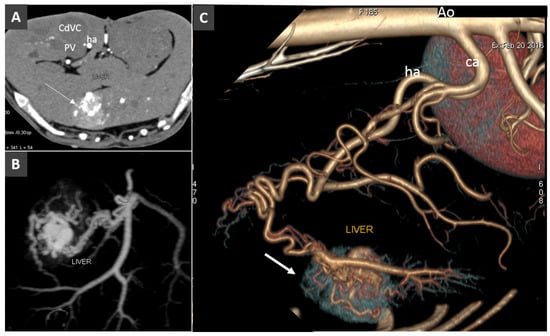

3.5. Anomalous Vascular Connections of the Portal Vein System

High-Flow Anomalous Portal Connections

3.8. Porto-Portal Collaterals or Cavernous Transformation of the Portal Vein